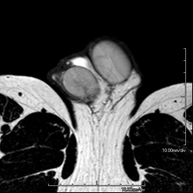

Prova diagnòstica no invasiva que consisteix en l'obtenció d'imatges d'alta definició anatòmica de la regió escrotal mitjançant l'ús d'un camp electromagnètic i ones de ràdio (amb un emissor i un receptor). No utilitza radiació ionitzant. De vegades s'ha d'emprar contrast paragmanètic (Gadolini) per completar l'estudi. S'utilitza per a l'estudi detallat dels testicles, per identificar possibles tumors i diverses patologies i per visualitzar alteracions de les estructures adjacents. - RM peniana

Prova diagnòstica no invasiva que consisteix en l'obtenció d'imatges d'alta definició anatòmica de la regió peniana mitjançant l'ús d'un camp electromagnètic i ones de ràdio (amb un emissor i un receptor). No utilitza radiació ionitzant. De vegades s'ha d'emprar contrast paragmanètic (Gadolini) per completar l'estudi. Normalment es realitza per estudiar la patologia peniana d'origen traumàtic i per visualitzar alteracions de les estructures adjacents.